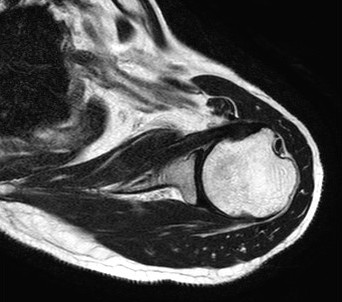

前立腺MRI

赤丸の部分が、がん

当センターの前立腺MRI検査では、さまざまな断面画像に加え、MRS(MRスペクトロスコピー)という特殊な方法を用いて検査を行っています。

「MRS」は体内の代謝物を検出する技術であり、前立腺ではクエン酸・コリンという2種の代謝物を測定することにより、がんの検出能向上や悪性度の評価に有用と言われています(正常ではクエン酸が豊富、がんではクエン酸が減少しコリンが上昇する)。しかし直腸ガスや生検後の出血の影響を鋭敏に受けやすいので、さまざまな検討を行い、その結果ルーチン検査として取り入れることに成功しました。